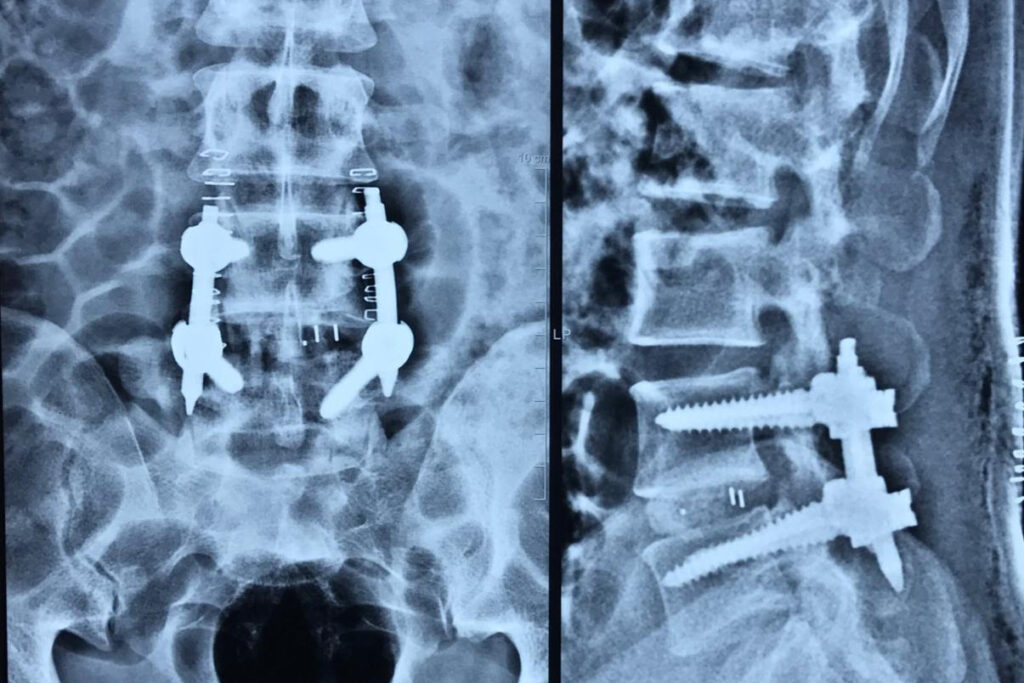

If you’ve been advised to undergo spine instrumentation or spinal fusion surgery, you’re likely wondering why this procedure is necessary—and